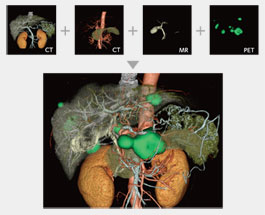

MULTI-MODALITY FUSION

Up to four different series from different phases or even modalities can be layered using varied opacity profiles.

The Multi-Data Fusion protocol highlights spatial relationships between objects that can assist in planning surgical procedures.